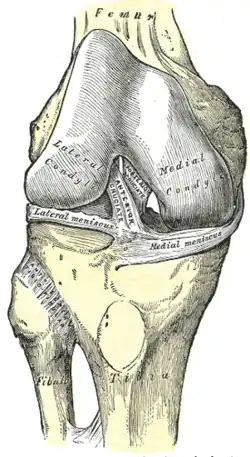

The knee joint is formed by three bones: the femur (thighbone), the tibia (shinbone), and the patella (kneecap). These bones are held together by ligaments, which are strong bands of tissue that keep the joint stable while an individual is walking, running, jumping, etc. There are two types of ligaments in the knee: the collateral ligaments and the cruciate ligaments.

The collateral ligaments include the medial collateral ligament (along the inside of the knee) and the lateral or fibular collateral ligament (along the outside of the knee). These two ligaments function to limit sideways movement of the knee.[6]

The cruciate ligaments form an "X" inside the knee joint with the anterior cruciate ligament running from the front of the tibia to the back of the femur, and the posterior cruciate ligament running from the back of the tibia to the front of the femur. The anterior cruciate ligament prevents the tibia from sliding out in front of the femur and provides rotational stability.[6]

There are also two C-shaped structures made of cartilage called the medial meniscus and lateral meniscus that sit on top of the tibia in the knee joint and serve as cushion for the bones.[1]

| Right knee, front, showing interior ligaments | Left knee, behind, showing interior ligaments |